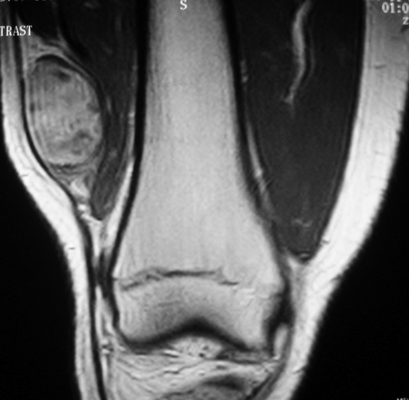

Исследование рыхлых структур конечностей проводят в случае:

нарушений двигательной функции;

болевого синдрома неясной этиологии;

нарушения чувствительности, слабости в руках и ногах;

абсцессов, флегмон, других воспалительных процессов в области конечностей;

Саркома мягких тканей бедра на МРТ